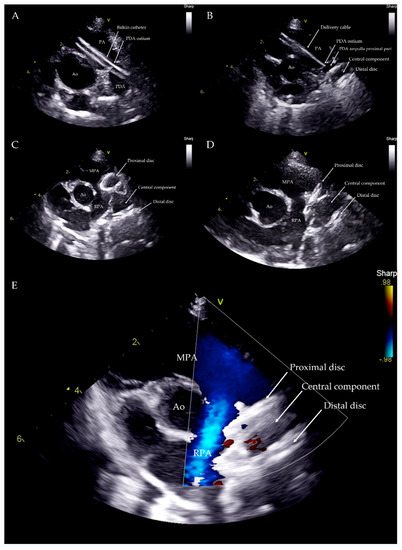

The device was introduced into the Balkin guiding sheath through the Check-Flo Valve and then advanced carefully until the distal disc was expanded into the descending aorta near the ductus. The partially-deployed AVP II, the attached delivery cable and the guiding sheath were gently pulled back simultaneously, until the distal disc engaged the aortic ostium of the PDA. The guiding sheath then was retracted while slightly pushing the delivery wire, allowing the central component of the device to expand into the PDA ampulla (Figure 3).

The proximal disk was then deployed in the main pulmonary artery with a firm but not excessive traction that was sufficient to create a slight distension of the proximal disc. This guarantees its position in the pulmonary artery, while the lack of waist in the device central component indicates that it is totally positioned in the ampulla and is not engaged in the ostium (Figure 4).

Correct positioning of the device was also evaluated during the procedure using transthoracic echocardiography, which also enables the presence or absence of residual flow to be analyzed throughout the device as well as its stability within the duct (Figure 5).

Figure 5. Transthoracic echocardiography from left parasternal cranial view during the procedure. Balkin catheter through the PDA (A). Distal disc and central component within the PDA ampulla (B). Distal disc and central component within the PDA ampulla and proximal disc within the PA just before the device deployment (C). Device released within the PDA structure (D). Device within the PDA with no residual flow (E). Ao: aorta; PA: pulmonary artery; MPA: main pulmonary artery; RPA: right pulmonary artery; V: probe marker.